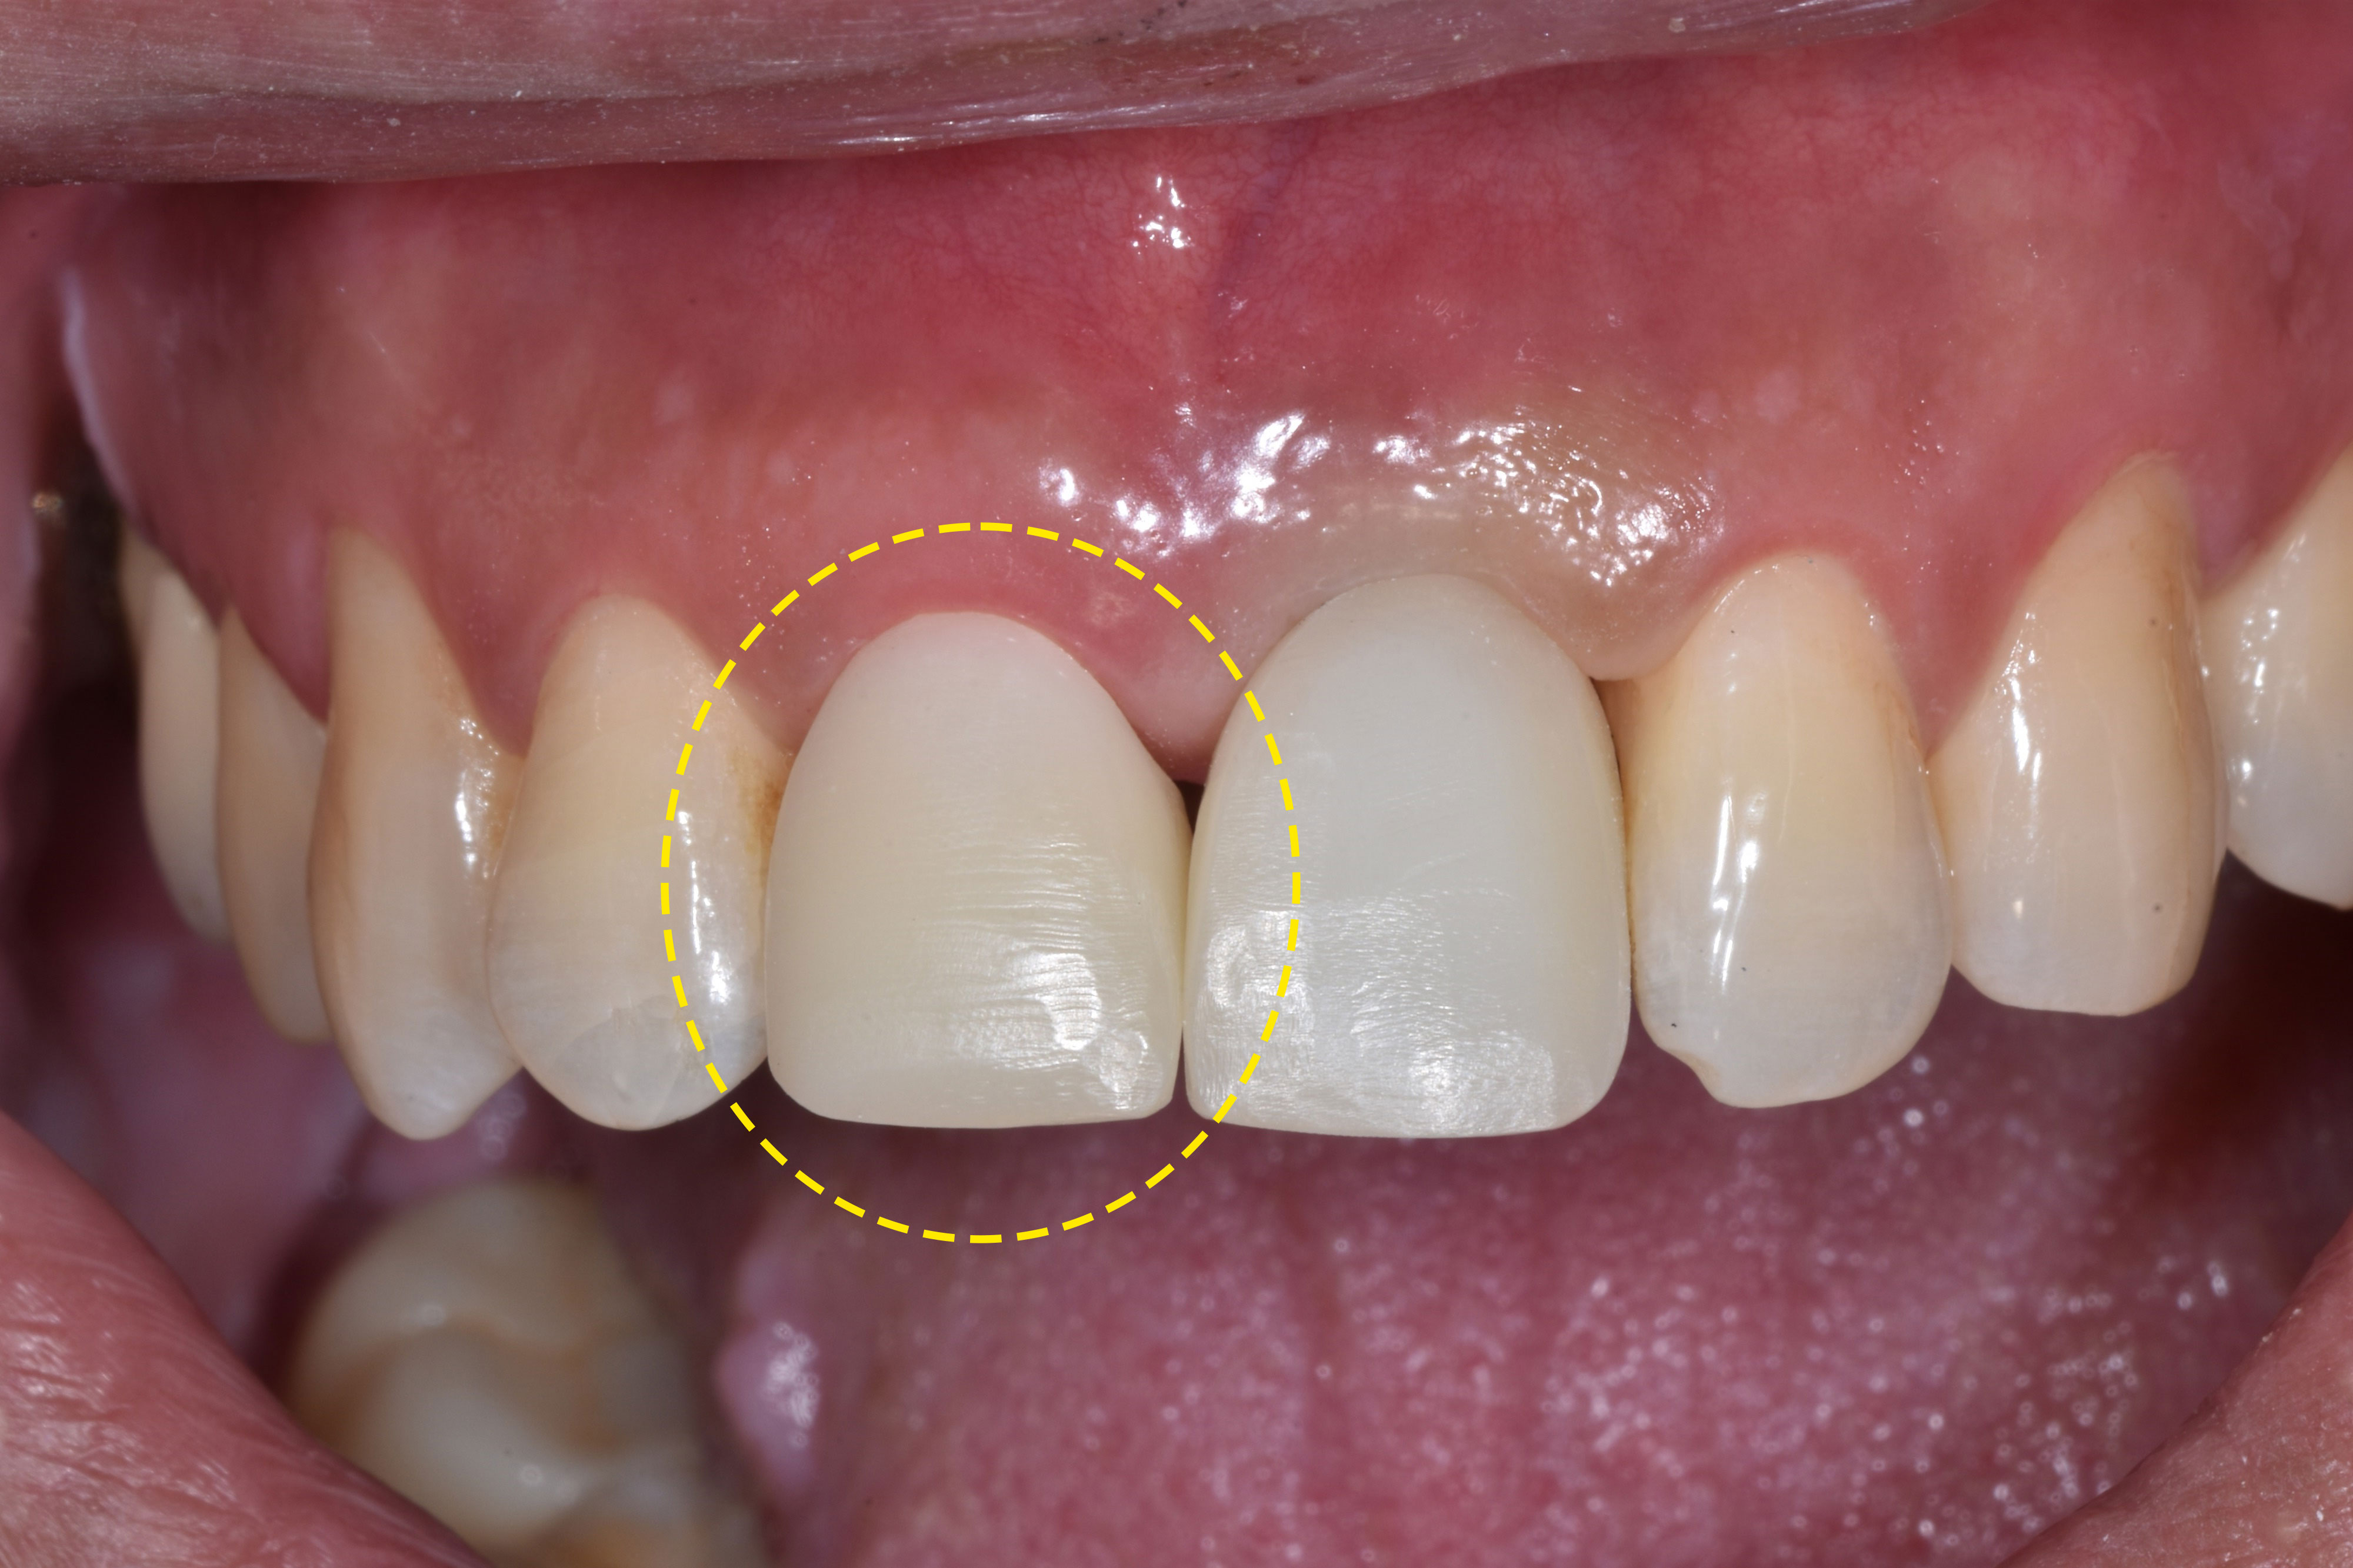

약 3개월 후 최종 보철물을 제작했어요.

두 치아 모두 최종 보철물이 들어가고

치료가 마무리 되었어요.🦷

앞니 치료는 기능적으로도 중요하지만

심미적인 부분 역시 빼놓을 수 없는데요.

아무도 당일에 치아를 빼고 치료한 지 몰랐을 정도로

임시치아부터 본 보철물까지 심미적이라 매우 만족한다고

하시며 감사의 인사를 전해주셨어요.